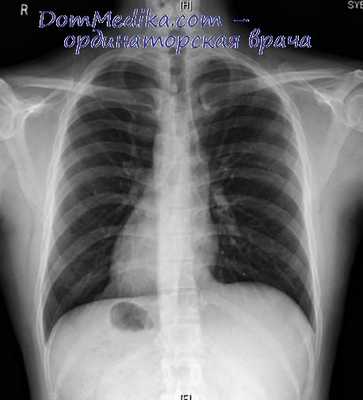

- Рентгенография ОГК. На рентгенограмме визуализируется смещение сердечной тени вправо, при комбинированных аномалиях изменяются контуры магистральных сосудов. Чтобы подтвердить транспозицию проводится рентгенография органов брюшной полости.